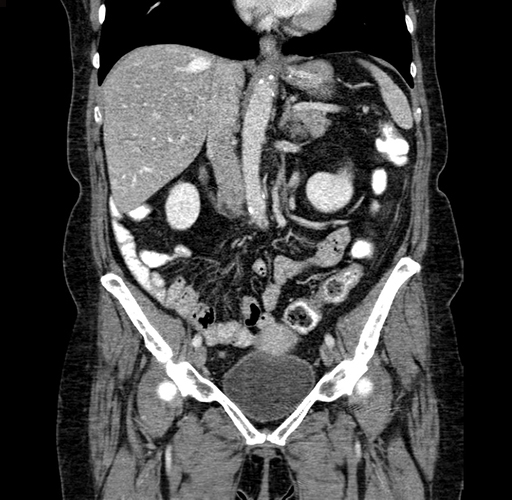

Coronal Venous